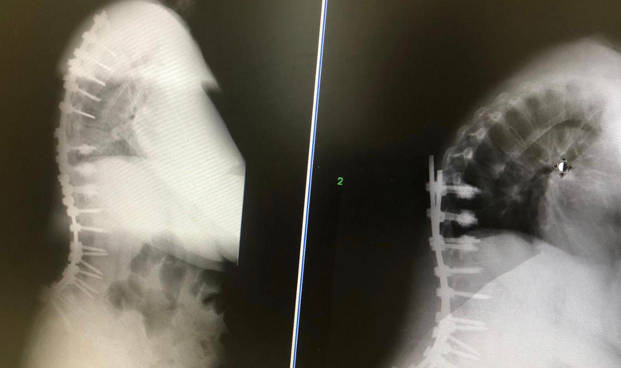

En esta radiografía valoraremos si la columna esta equilibrada, es decir al mirar la radiografía de frente el peso de la cabeza tienen que recaer sobre la pelvis. También miraremos la radiografía del perfil de la espalda y valoraremos si el peso de la cabeza recae sobre el sacro. Para ello lo que hacemos es trazar una línea desde el centro de la vértebra C7 y vemos a que altura de la pelvis cae. Si la línea de la vértebra C7 cae muy por delante de la pelvis tendremos una pérdida del equilibrio sagital. Pincha en este enlace si estas interesado en saber la importancia del equilibrio sagital como origen del dolor de espalda.

Fusiones amplias. Las fusiones amplias se reservan para los casos más extremos y cuando la escoliosis esta desequilibrada. En estos casos trataremos de corregir la forma de la escoliosis y tratar de darle una forma a la columna para recuperar el equilibrio. Se trata de cirugía muy agresiva y que presentan complicaciones en el 30-50% de las ocasiones. Hay estudios que dicen que al menos en 30% de los pacientes va a necesitar una cirugía para corregir complicaciones.

La cirugía de corrección de escoliosis del adulto consiste en realizar grandes incisiones, en las que ponemos muchos tornillos, además realizamos cortes en las vértebras denominados osteotomías para tratar de modificar la forma de la columna.